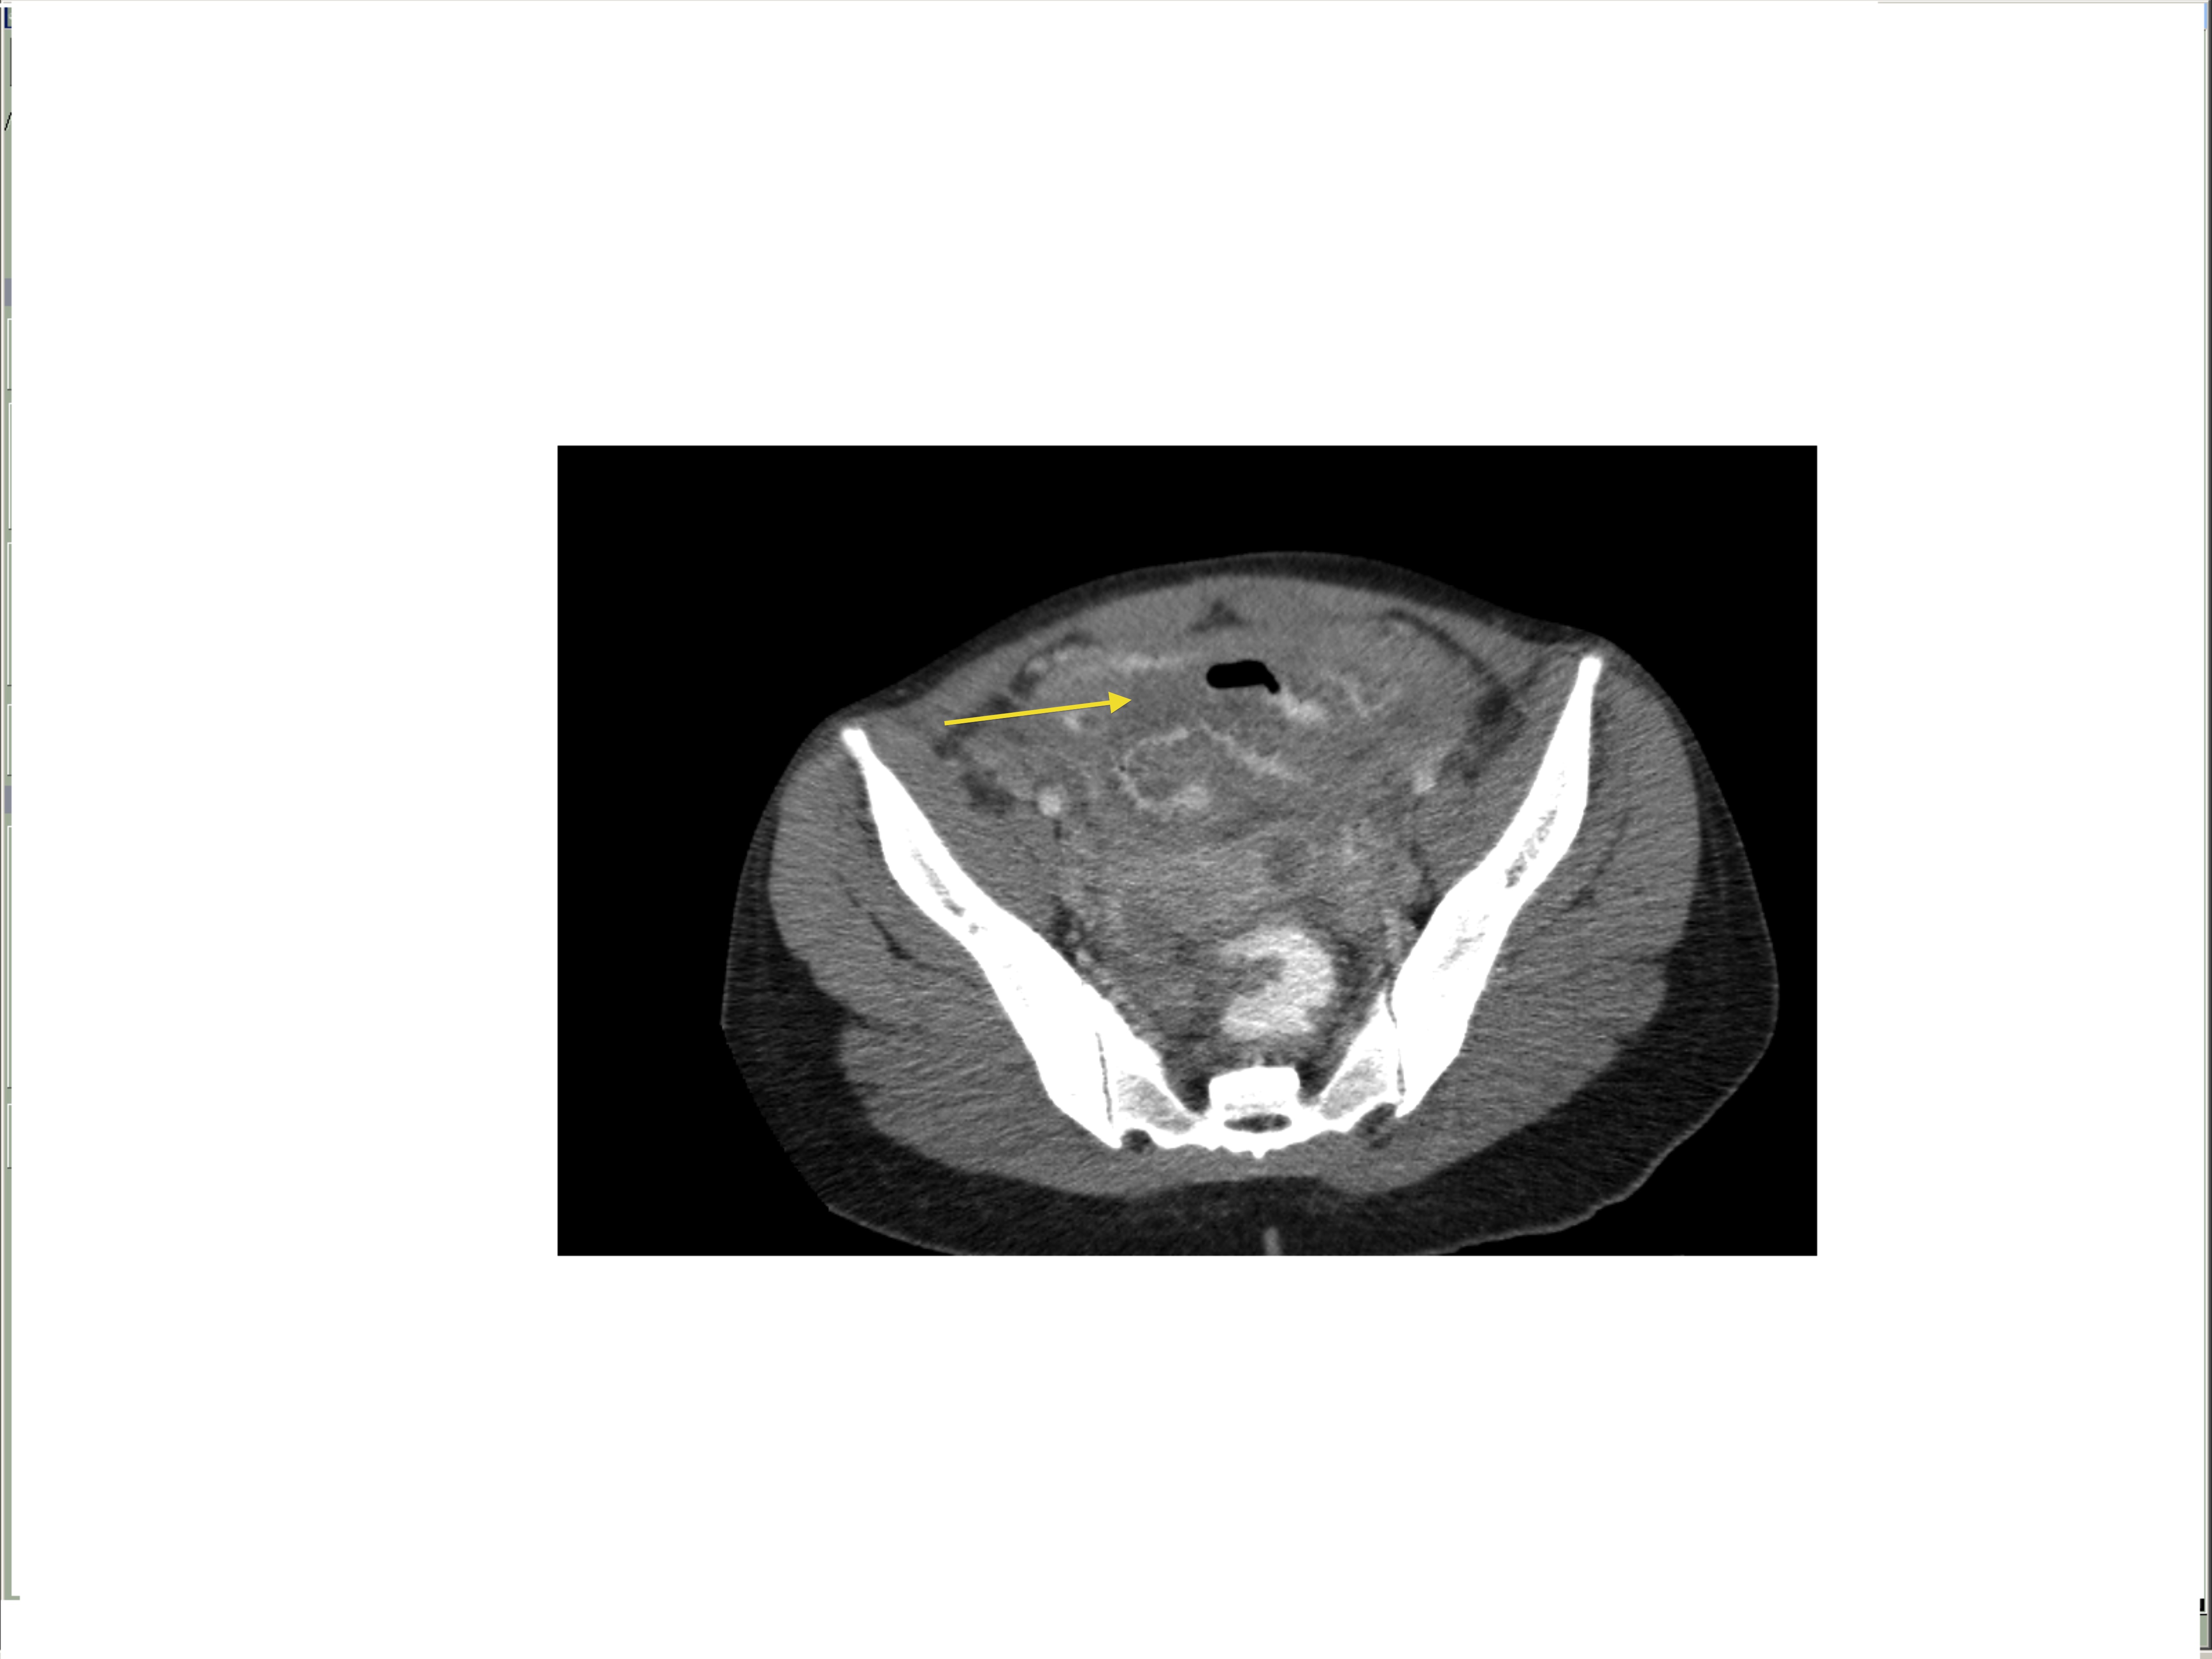

Small bowel obstruction is a common clinical presentation that presents a diagnostic conundrum. Over the last 2 decades, there has been a paradigm shift in the radiological investigation of small bowel obstruction (SBO) and in the indication for and timing of surgical intervention. Cross sectional imaging (predominantly computed tomography) has largely replaced the widespread use of radiographic small bowel follow-through studies as the imaging modality of choice for SBO. This article illustrates the current imaging modalities available for diagnosis of small bowel obstruction. (Full text available online at www.medpharm.tandfonline.com/ojfp) S Afr Fam Pract 2015; DOI: /10.1080/20786190.2014.977052